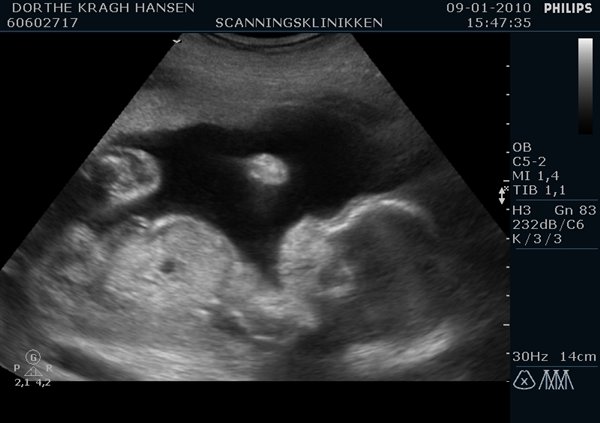

Men nu har jeg set bebsen igen og med egne øjne set, at det ER en bette pige der ligger og bokser rundt i maven på mig

Hun er bare så sød

Første billede siger sig selv og andet er...ja hendes lille tissetrold